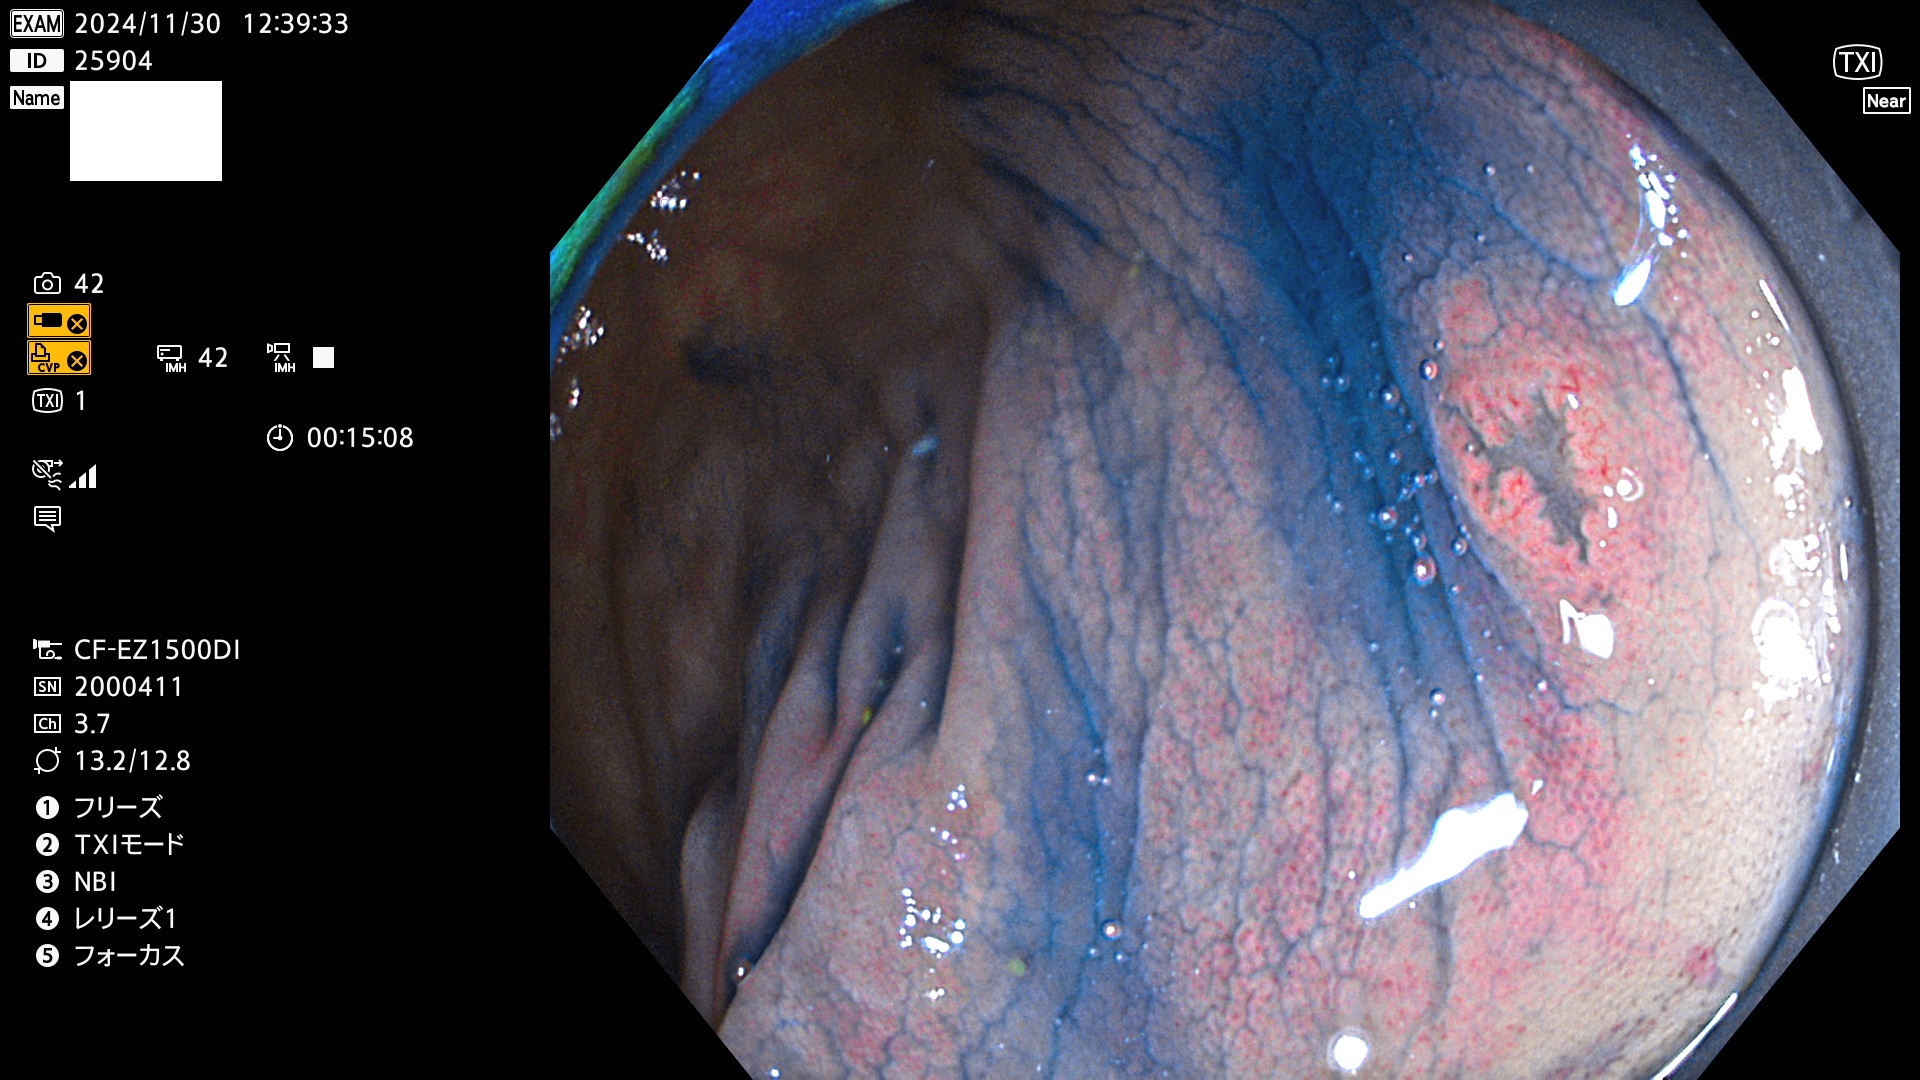

今週のUb、Uc型腺腫

完全に平坦な物をUb、陥凹している物をUcと呼びます。最も発見が難しく危険な病変です。

毎週の検査(木・金・土・日)に発見されたUb、Uc型・腺腫を、その週の日曜の夜にUPし1週間、提示します。

抽出の対象期間 2024年11月28日〜12月2日の5日間(60件の検査)9件 (9/60=15%)